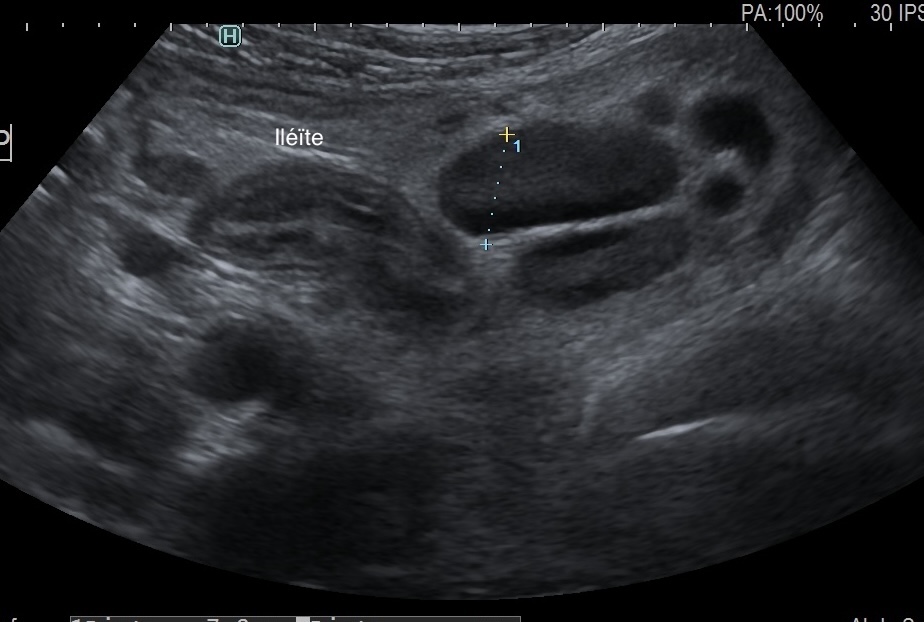

Iléïte et gros ganglions mésentériques